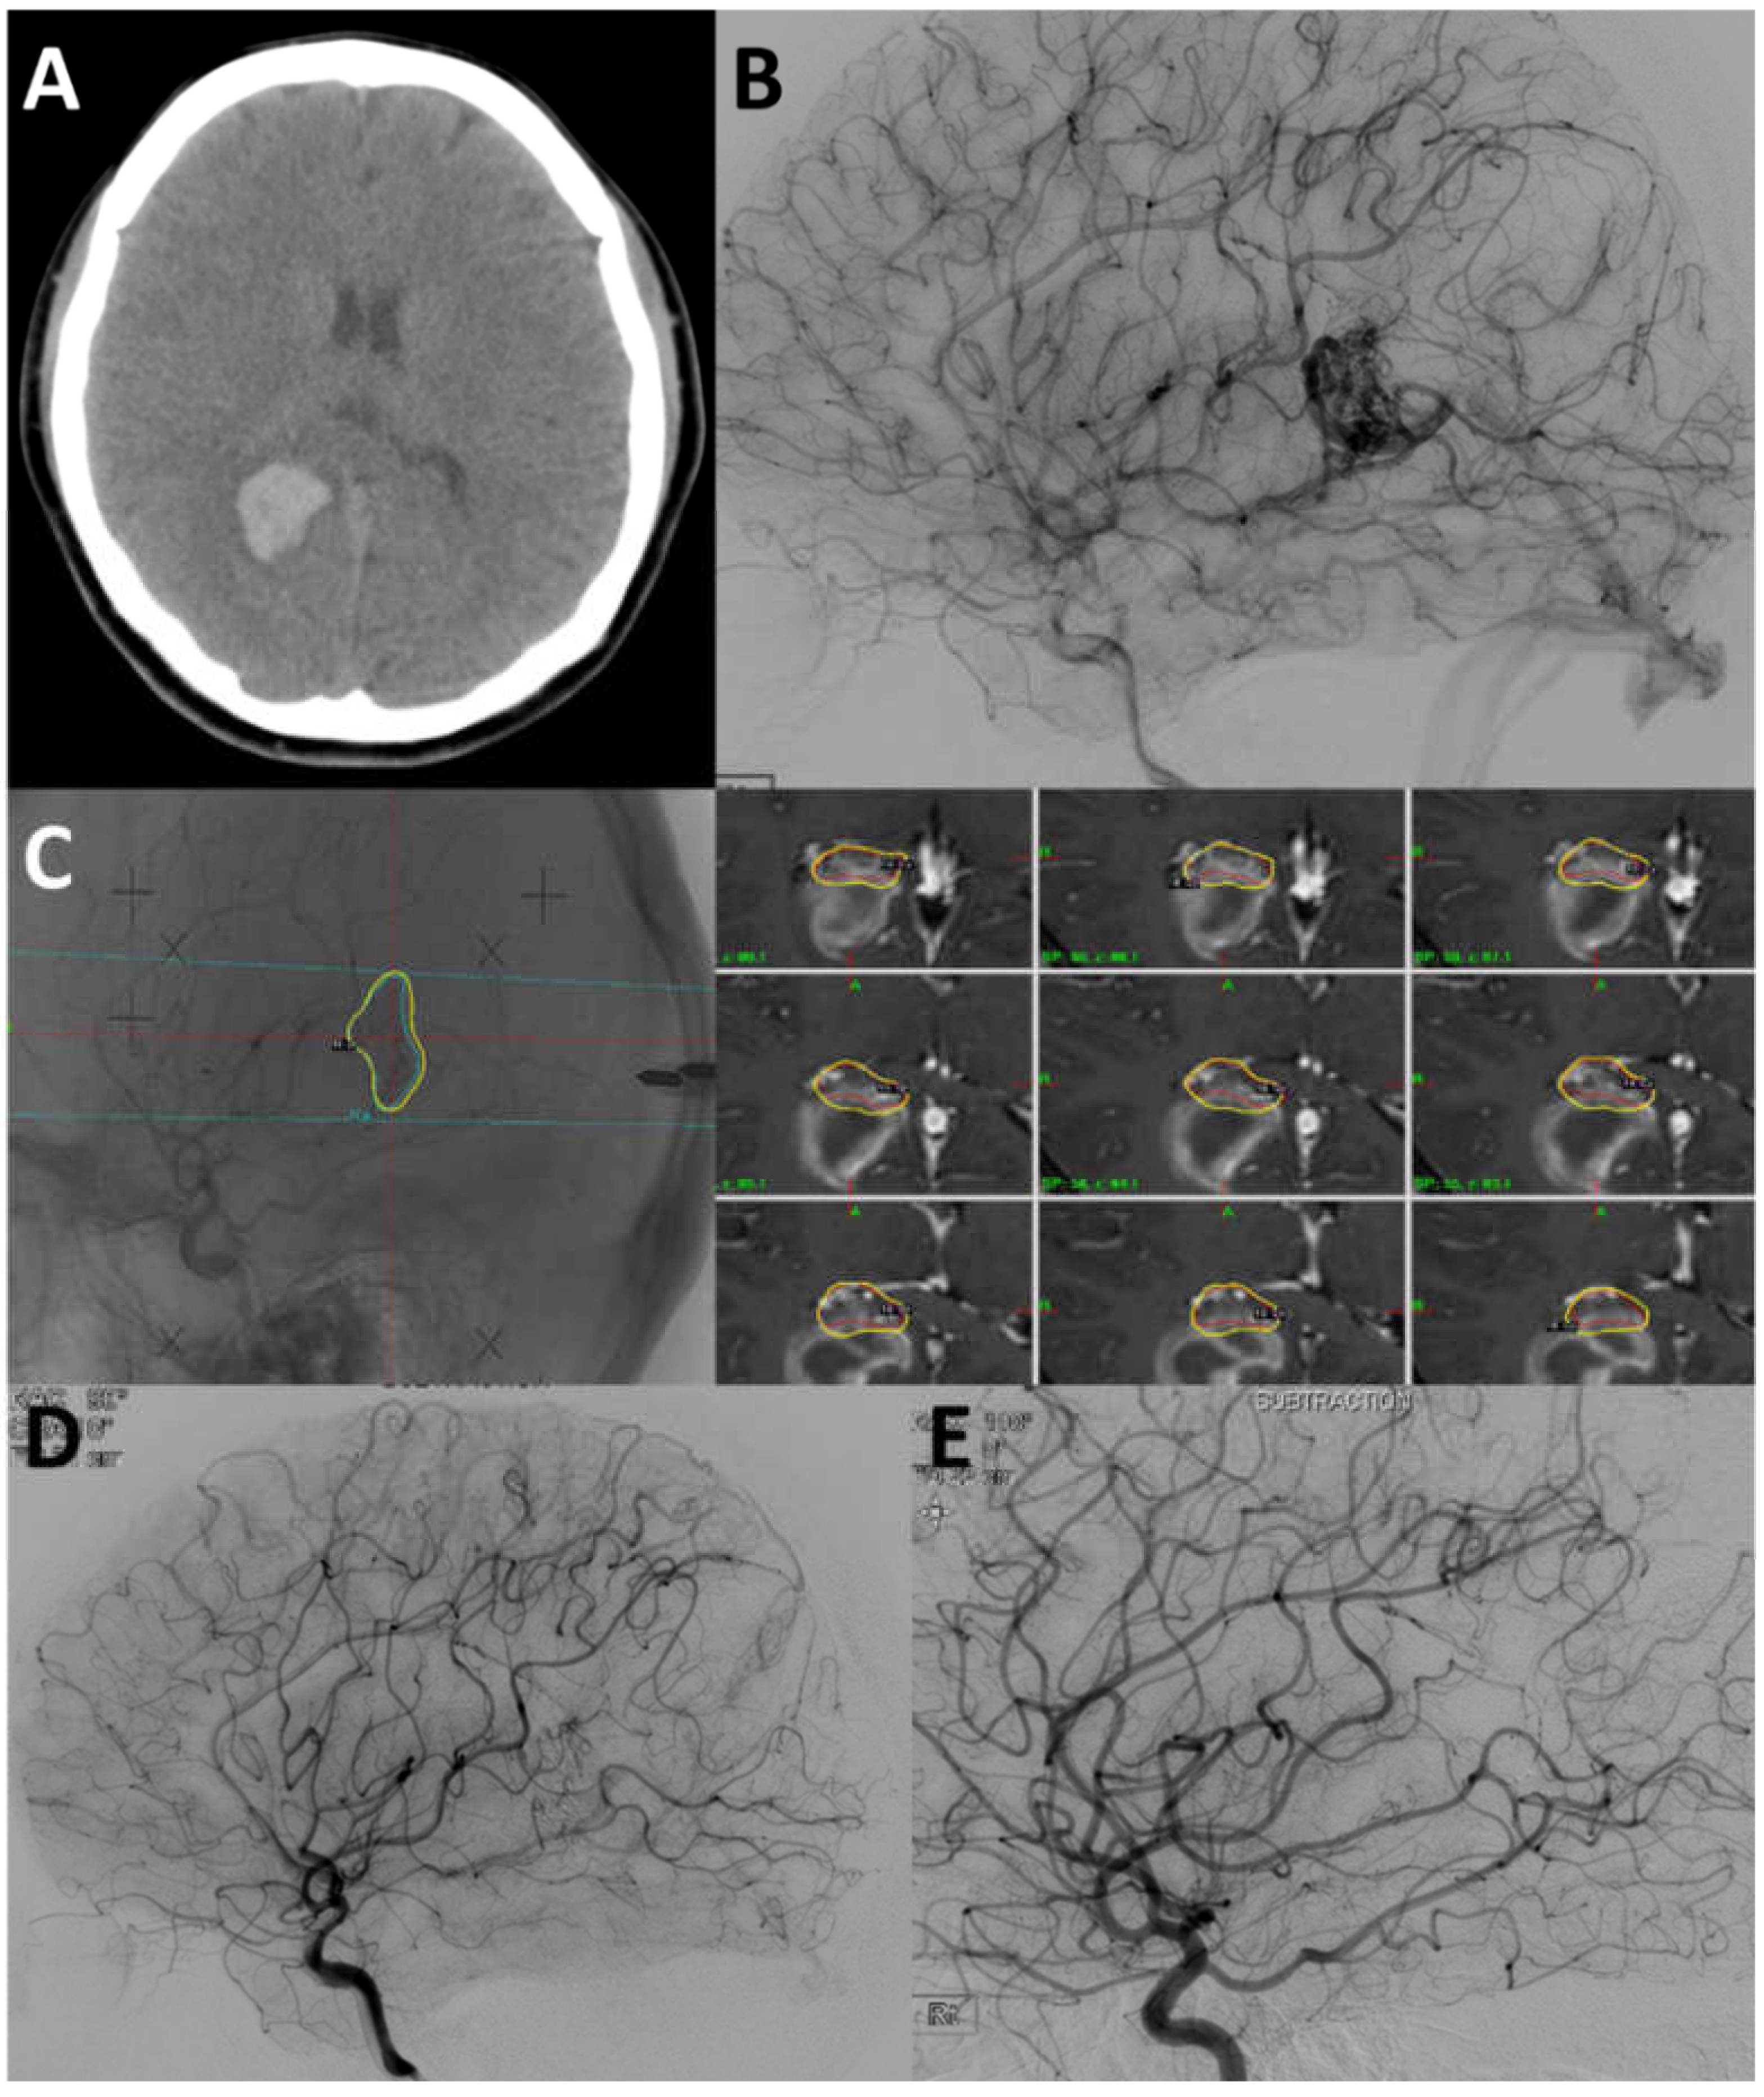

4.2. Case 2